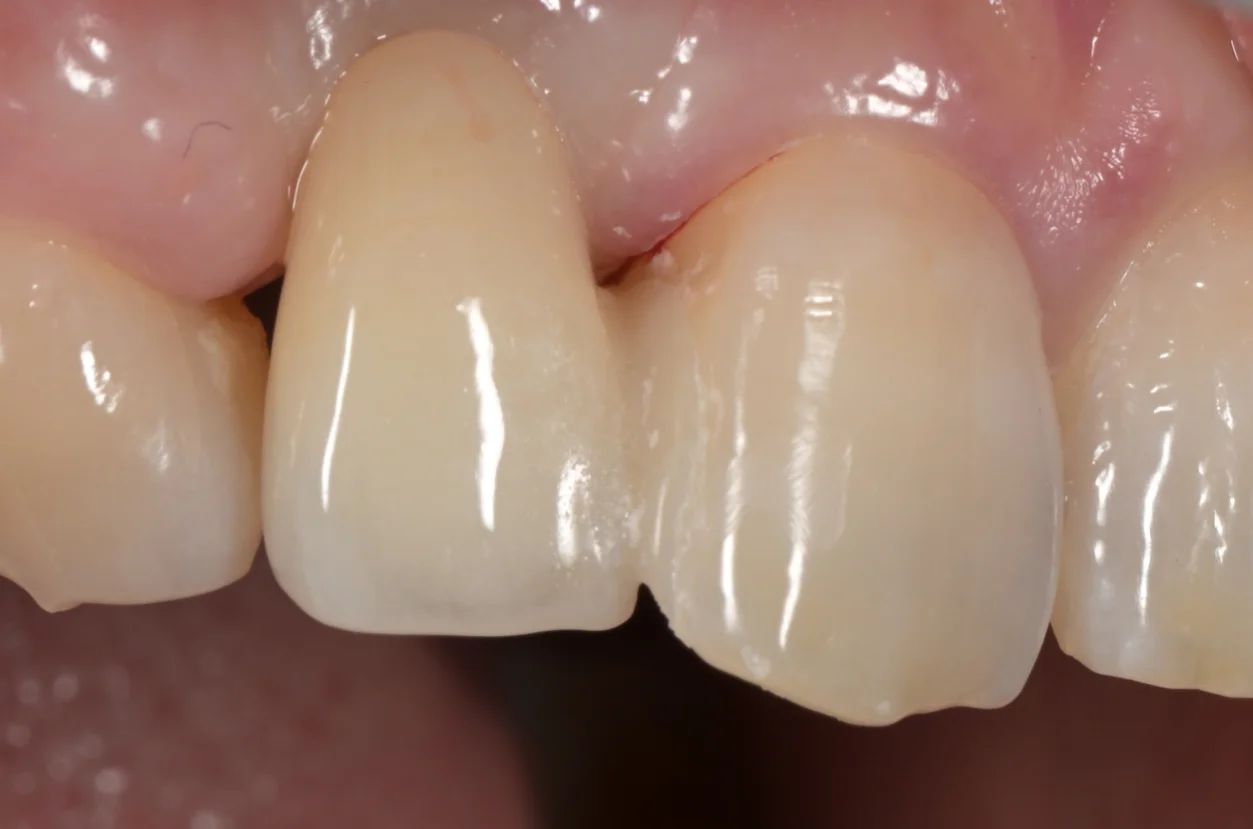

斜めから見たのがこちらになります。

セメントでつけた後にそのセメントを除去した時の写真です。

隙間も段差もなく綺麗にハマっているのがわかると思います。